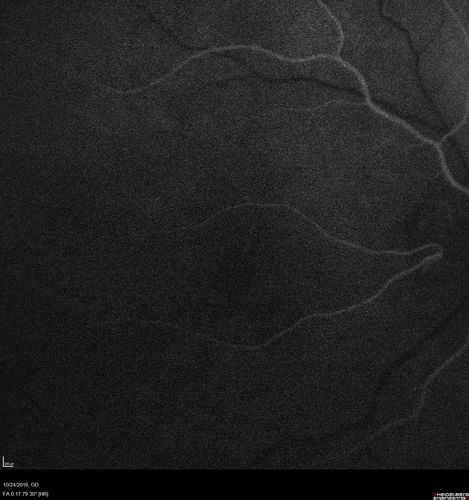

Late Onset Retinal Degeneration (L-ORD)

55 year old with acute vision loss from a CNVM in the right eye. He responded to Lucentis therapy. His mother and her family has been confirmed genetically to have L-ORD and were part of the early reports.